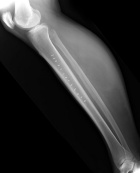

D.B. – 69 year old white female with five year history of non-tender, slowly enlarging right calf mass

Zoom image: Radiological image Radiological image.